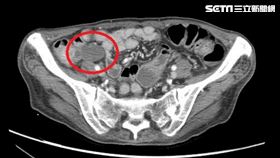

瀉10年體重剩37公斤 闌尾癌作祟

60歲僅37公斤的女性因頭暈、嗜睡送急診,意外發現造...